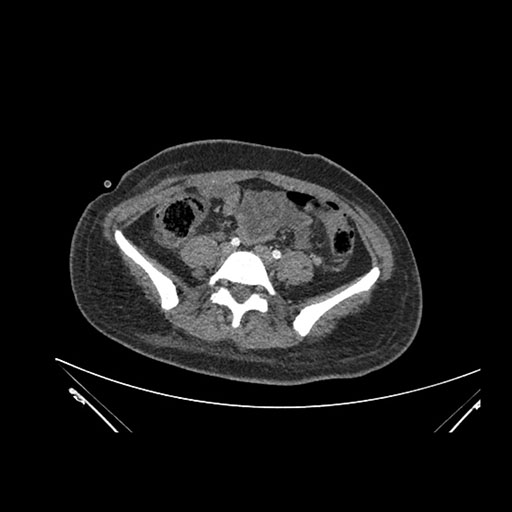

Coronal Venous

Imaging analysis

Based on initial findings, which issue(s) would you be most concerned about?